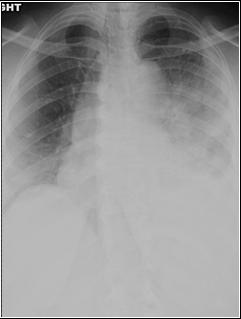

Left lower lobe & lingular pneumonia